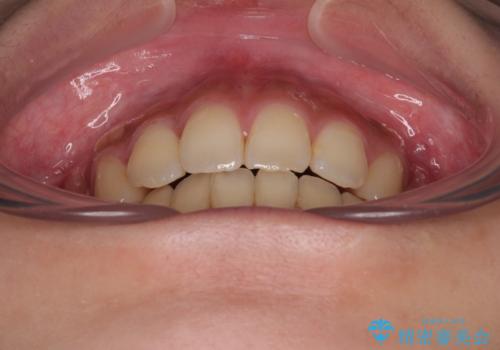

上下の前歯が接触する仕上がりとなったので、横顔の印象が大幅に改善されました。